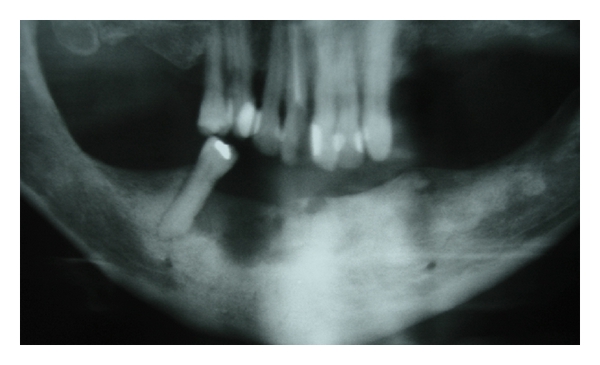

Case 1. A 77-year-old white female was seen at the Oral Medicine Clinic of the Federal University of Alfenas (UNIFAL-MG) with an asymptomatic, smooth surfaced, normal colored tumor on the anterior mandibular alveolar ridge, with two months evolution. A drainage point with purulent material was also present (Figure 1(a)). The patient’s medical history was unremarkable and no changes were noted on extraoral examination. Radiographic examination revealed osteolysis and bone sequestration on the mandibular alveolar ridge (Figure 1(b)). Based on clinical and radiographic findings, a provisional diagnosis of osteomyelitis was rendered. The patient was given amoxicillin (500 mg, three times/day) for 15 days and subsequently underwent excision of the bone sequestrum and curettage of the granulation tissue (Figure 2). The material was submitted to histopathological examination which revealed nonviable bone and a mixed inflammatory infiltrate of lymphocytes and plasma cells, confirming the diagnosis of chronic suppurative osteomyelitis. The area healed appropriately within one month (Figures 3(a) and 3(b)). The patient has been under follow-up for 5 years with no signs of recurrence.

(a)

(b)